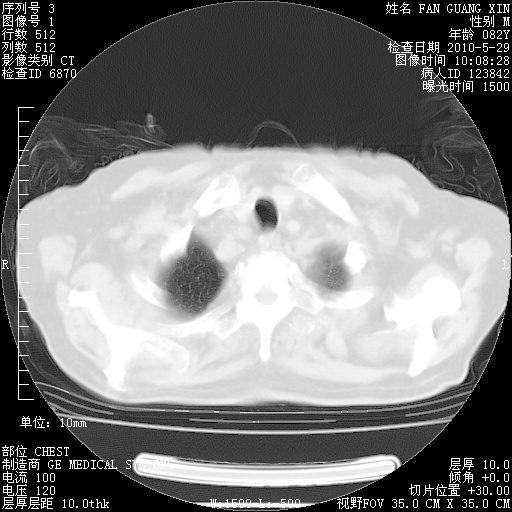

再治疗10天后的肺部CT 纵膈窗